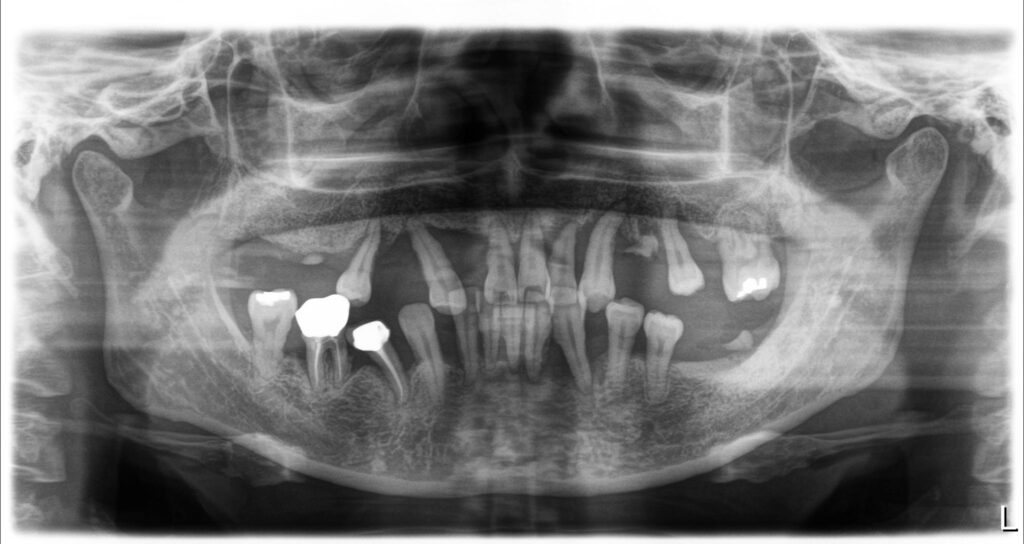

위에 보이는 엑스레이 사진은 심한 치주염으로 일부의 치아는 자연발치되고 남아있는 치아들은 자기 자리를 찾지 못하고 위치들이 많이 바뀌어 있는 모습이 보입니다. 중요하게 보아야 하는 부분은 뼈 속에 들어있는 치아뿌리의 양입니다.

보이는 파노라마 사진의 치아들의 뿌리들은 대부분 턱뼈 속에 거의 조금만 위치하고 대부분은 뼈가 다 녹아있는 것이 보입니다. 그렇게 되면 치아들이 많이 흔들리게 되고 그러면서 치아가 자기 자리를 유지하지 못하고 솟고, 쓰러지고, 벌어지게 됩니다.

이런 상태까지에 이르기에는 많은 시간이 필요합니다. 그렇기 때문에 조금이라도 빨리 치료를 하셔서 치아를 뽑지 않도록 하시는 것이 좋습니다.